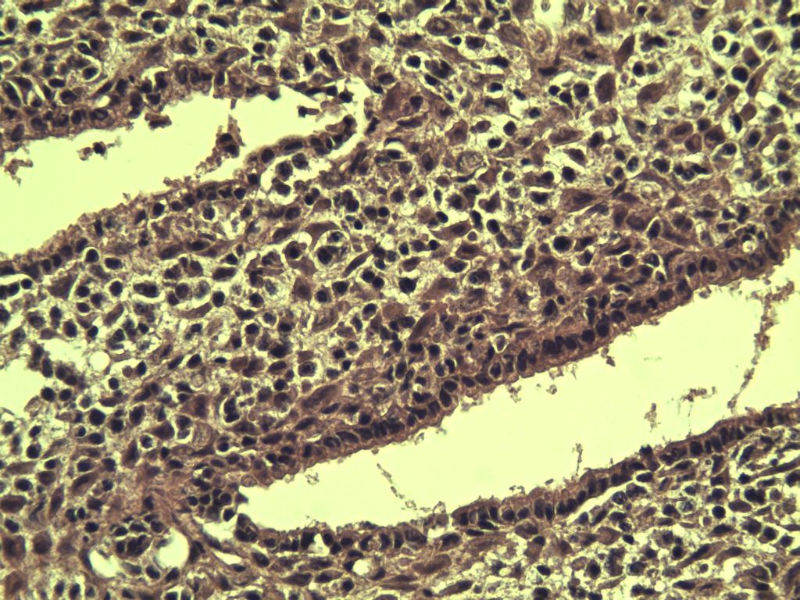

这是另外一个 40岁 经期延长 流血量增多 半年 这是蜕膜样变吧 有什么意义吗? 要报告不?